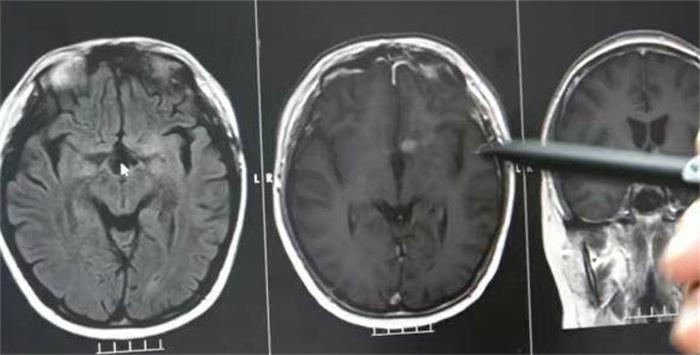

带着彬彬来到医院经过专家会诊,才确认彬彬出现异常行为,是因为他患上了混合型生殖细胞肿瘤,当时医生就做出了放射治疗的决定,认为放射治疗对于孩子的危害比较轻,又能够尽快控制住他的病情,现在每天喝水量控制在三升左右,仍然在医院接受化疗,并且头上的病灶已经通过手术切除,恢复的比较好。